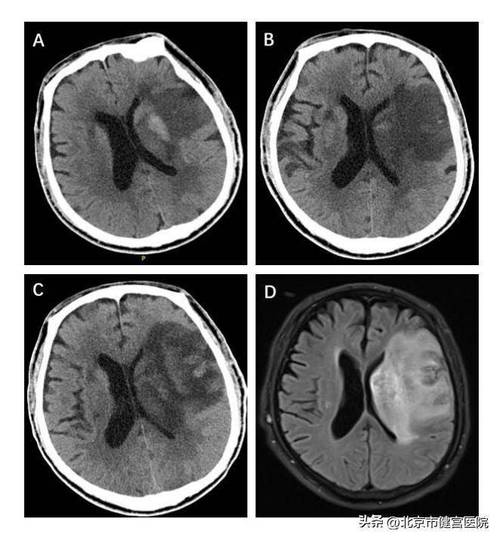

第二阶段:发病后6-24小时

随着缺血时间的延长,细胞水肿加剧,并开始出现血管源性水肿,一些早期征象会变得更加明显。

常规CT平扫表现:

- 脑实质密度降低:这是梗死核心区开始出现不可逆损伤的标志,缺血区域的脑组织因为细胞崩解、水肿和蛋白质分解,密度开始逐渐低于周围正常脑组织,但在24小时内,这种密度差异通常仍然很轻微,不仔细观察容易漏诊。

- 占位效应开始显现:随着水肿范围的扩大,梗死区域可能出现轻微的脑室受压或中线结构轻度移位,但大面积梗死导致的明显中线移位通常在24小时之后才会出现。

早期间接征象更加清晰:

- 脑沟消失/变浅范围扩大,程度加深。

- 豆状核模糊征或岛带消失征(见下文)变得更加明显。

- 岛带消失征:这是大脑中动脉供血区梗死的另一个高度特异性早期征象,岛叶(脑岛)的皮层密度通常比邻近的额叶和顶叶皮层略高,当大脑中动脉闭塞导致岛叶缺血时,其密度会迅速降低,与周围皮层密度变得一致,形成“消失”的假象,这个征象在发病后6-12小时左右出现率较高。